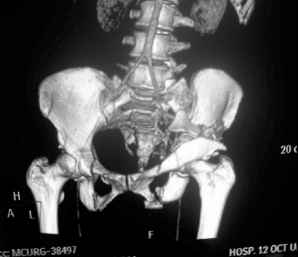

I'm posting this case on behalf of Dr. Pedro Caba, he is unable to post but able to read. 41 yo female , fall from 10 meters five days ago. Hemodynamically unstable on admission treated by angio and embolization and skeletal traction, with no external support. No associated injuries. Based on CT scan the pt has a both column fracture with conminuted dome and displaced anterior column and a sacral Denis 1 fracture with a displaced left ala. I think the best approach for the acetabular fracture is ilioinguinal with Smith-Petersen extension but don't know exactly the sequence . Will you start with the sacral fracture? Which technique? Thanks in advance Pedro Caba Unidad de Trauma Hospital 12 de Octubre Madrid Spain

This complex and displaced sacral injury is likely an H pattern...2 hemipelvic components, an upper sacral component which remains attached to the lumbar spine, and a caudal sacral component...there are typically anterior ring injuries as well...in this patient's example, the left sided acetabulum also has been exploded.

Most H pattern sacral fractures have the transverse fracture limb of the "H" at the upper-second sacral segment junction or disc region...some fracture thru the second segment, and some or at other sites...but most yield thru the upper-second sacral segments junction...with variable traumatic associated neurological findings.

The hemipelvic components' displacements depend on their instability...this patient's left side seems to be the worst.

The kyphosis and anterior translation of the upper sacral segment distorts the safe area for iliosacral screw usage...the imaging allows the surgeon to preoperatively plan if iliosacral screw fixation is a safe possibility.

For this patient (according to the limited imaging available), it would seem that a combination of lumbo-pelvic fixation along with transiliac transsacral fixation is optimal...BUT the left sided pelvic implants must be applied in consideration of and in anticipation of the necessary acetabular fixation implants.

So you are correct, this pattern likely needs a great reduction and a powerful fixation construct to be durable...but the operative exposure and implants must be planned carefully if the acetabular fracture is to be accurately reduced and well stabilized.